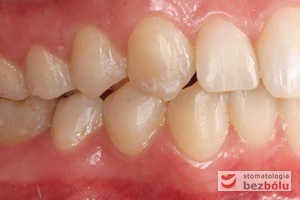

Pacjentka lat 22 zgłosiła się do naszej placówki celem podjęcia leczenia ortodontycznego. Głównym oczekiwaniem pacjentki była poprawa estetyki uśmiechu oraz brak ekstrakcji zębów na drodze do jej uzyskania. Ze względu na liczne stłoczenia zębów w górnym i dolnym łuku, dość duży materiał zębowy w porównaniu z bazą kostną, a także zgryz przewieszony boczny prawostronny po dokładnej analizie cefalometrycznej oraz analizie modeli diagnostycznych zastosowano leczenie bezekstrakcyjne z wykorzystaniem strippingu jako alternatywy dla usuwania zębów, mającego na celu uzyskanie miejsca w łuku na uszeregowanie zębów. Po fazie aktywnego leczenia trwającego 18 miesięcy zastosowano leczenie retencyjne w postaci szyny retencyjnej w łuku górnym oraz retainera stałego w łuku zębowym dolnym klejonego od kła do kła.